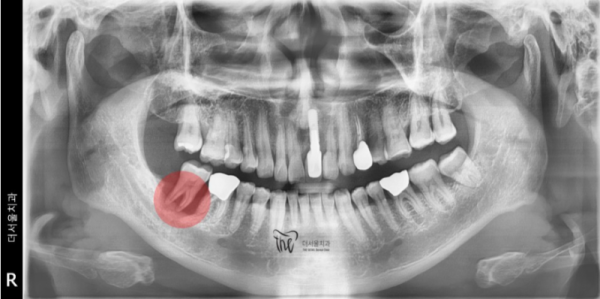

네비게이션 임플란트는 CT를 통하여

환자분의 턱 뼈 속을 단층촬영하여 신경관, 상악동의 위치를

파악하여 뼈 속의 상황을 컴퓨터를 통해 정확히 파악하여

임플란트를 어떤각도, 어떤 깊이로 심으면 좋을지 미리 결과를 확인하는 방식을 말합니다.

바로 이 화면이 성남치과 더서울치과의

내비게이션 임플란트의 화면입니다. 환자분의

뼈 두께, 신경관의 위치를 확인할 수 있으며 어떤크기의

임플란트를 어떤 깊이로 심어야하는지 확인할 수 있습니다.